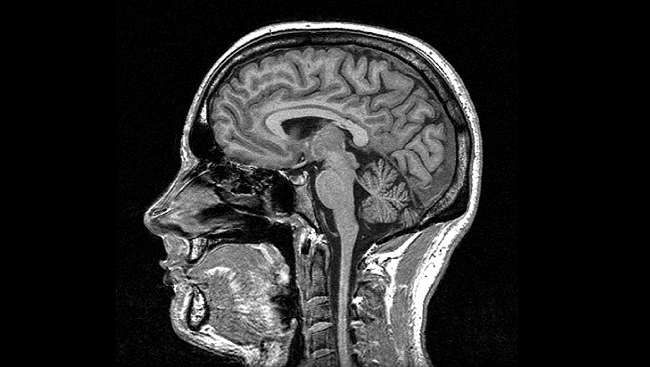

Multiple Sclerosis: MRIs Compared After Low Saturated Fat Diet

In July 2015, two MRIs led to a diagnosis of Relapsing Remitting Multiple Sclerosis for me. I had a follow up MRI done in December 2015, while I was travelling. After being back in the United States, I met with my neurologist to have the MRIs compared. I was hoping for some insight into the… Continue reading Multiple Sclerosis: MRIs Compared After Low Saturated Fat Diet